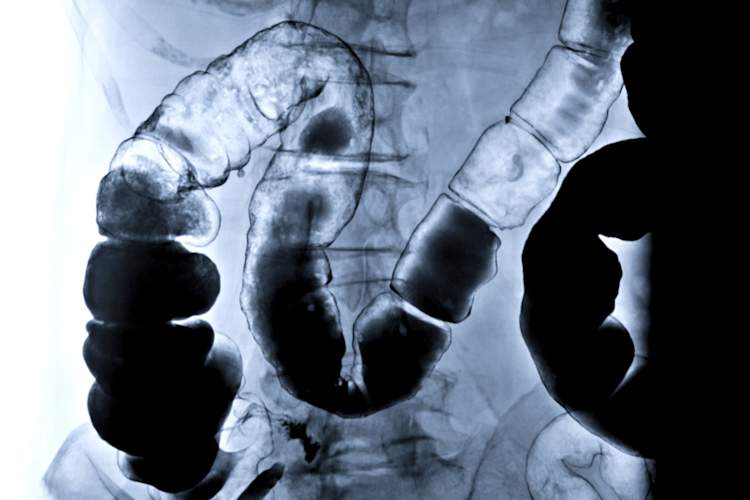

让我们来谈谈克罗恩病检验和诊断

这将是巨大的,如果你有克罗恩单一的考试可以证实。当然,这并不是说简单,但低于可以一起测试,以提供您的健康更清晰的画面。